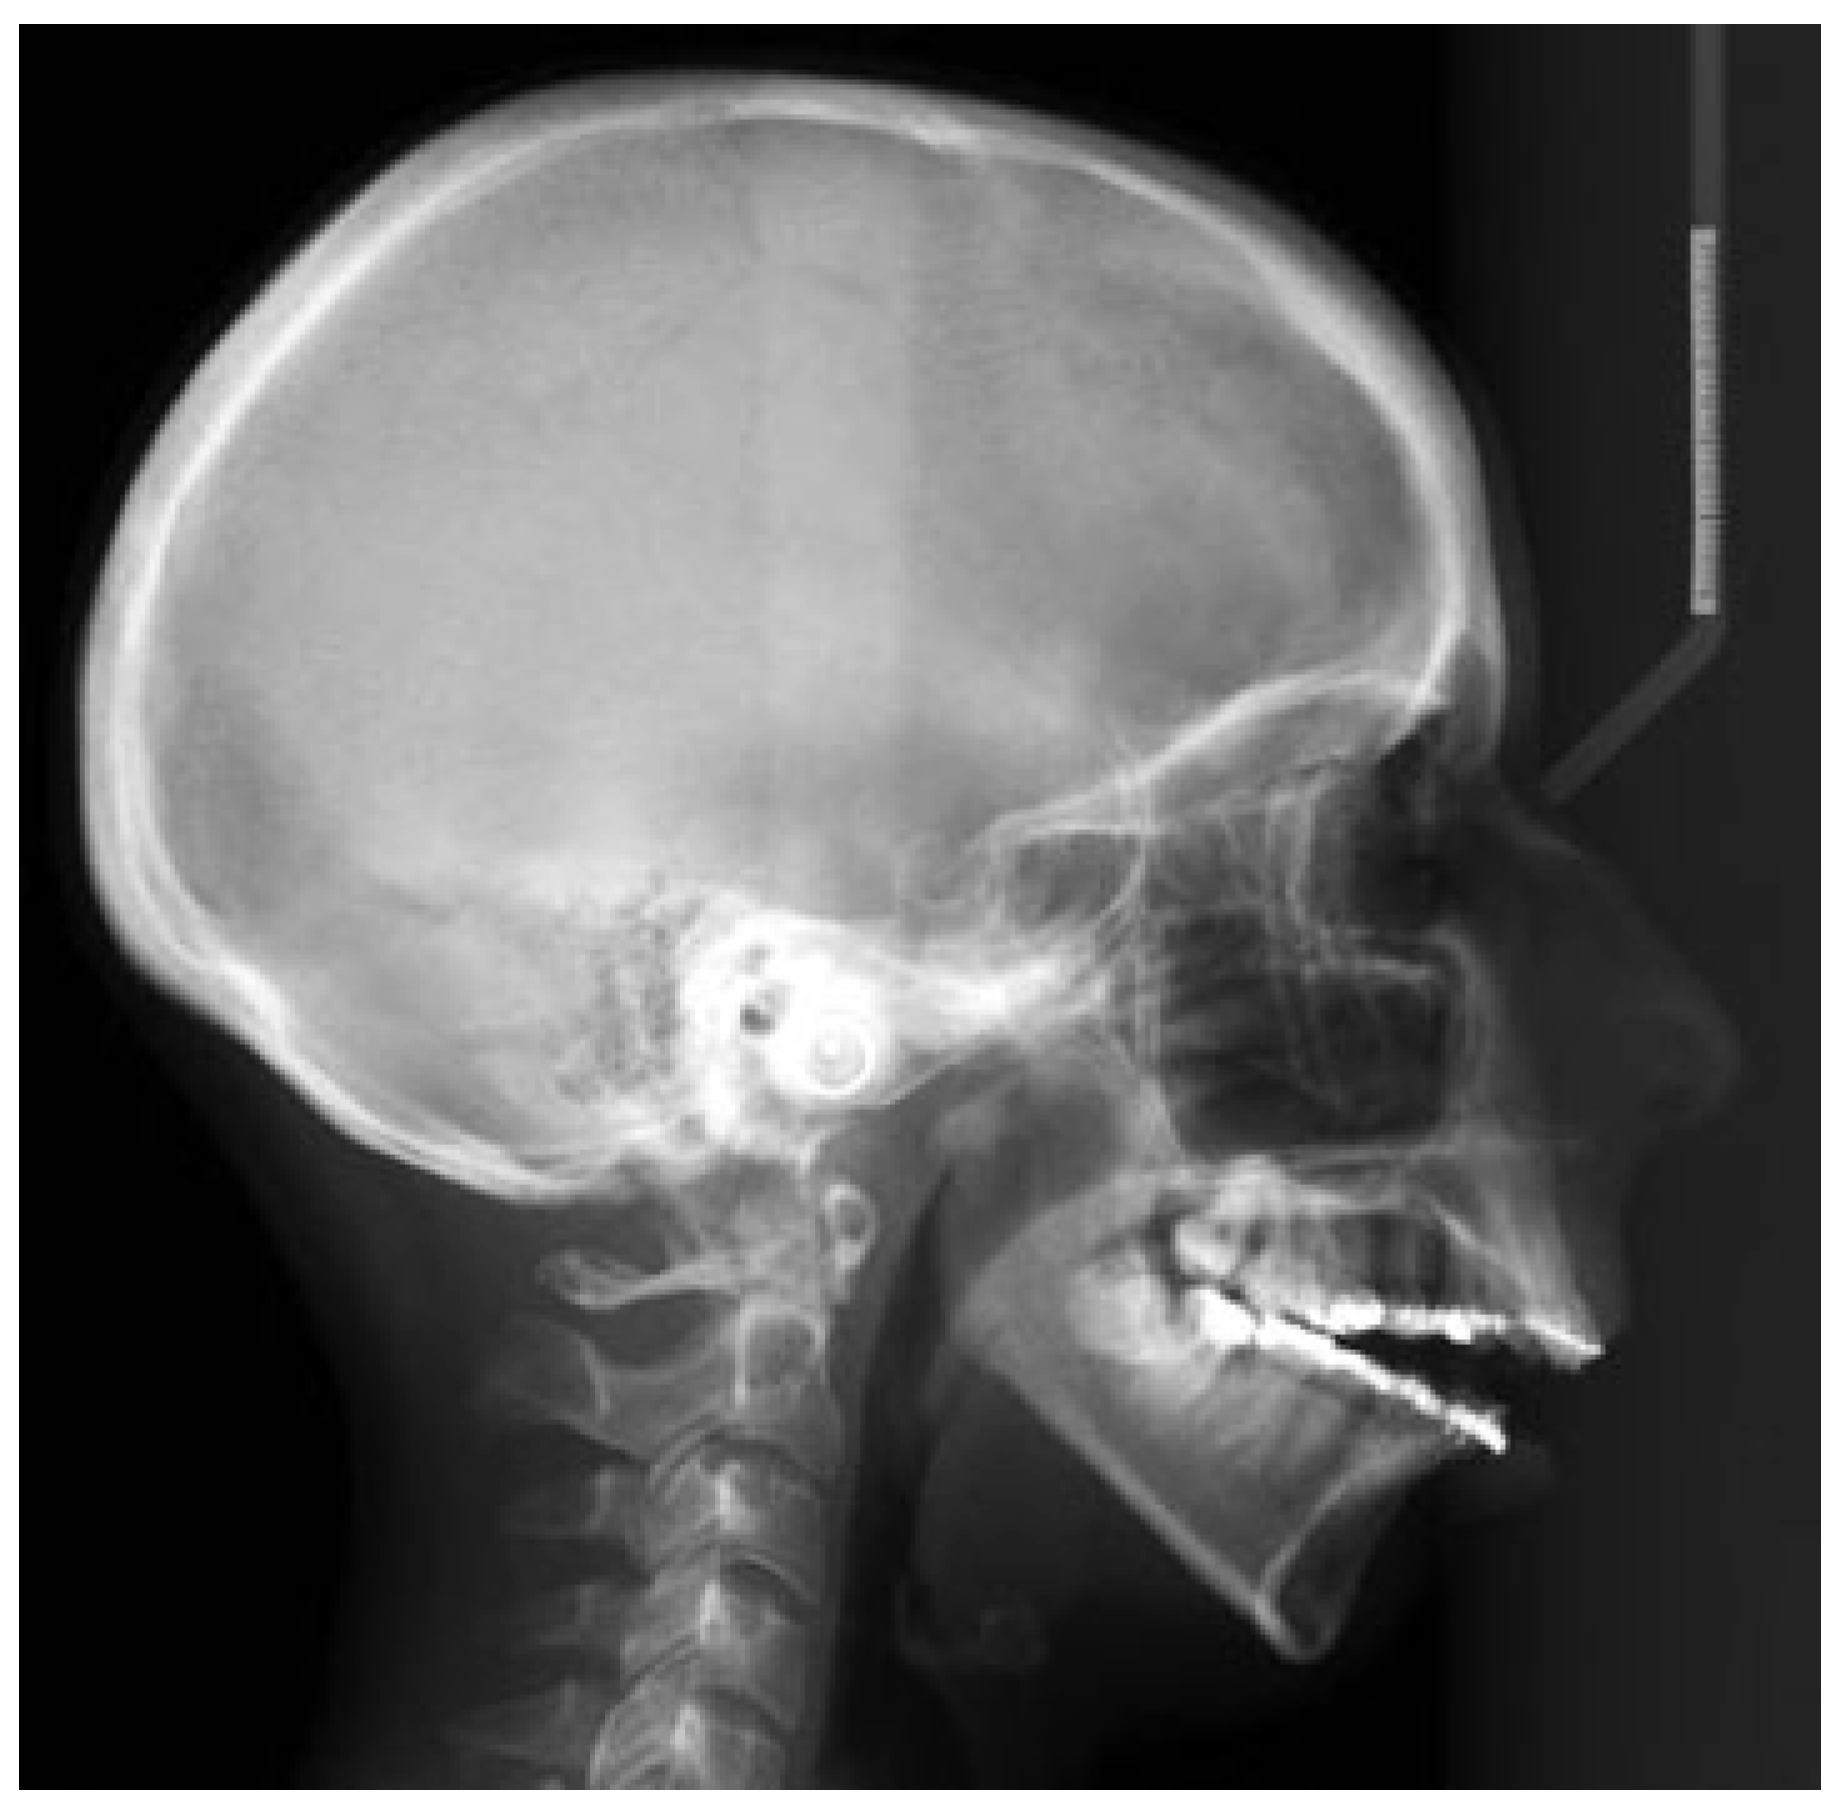

Radiological Examination